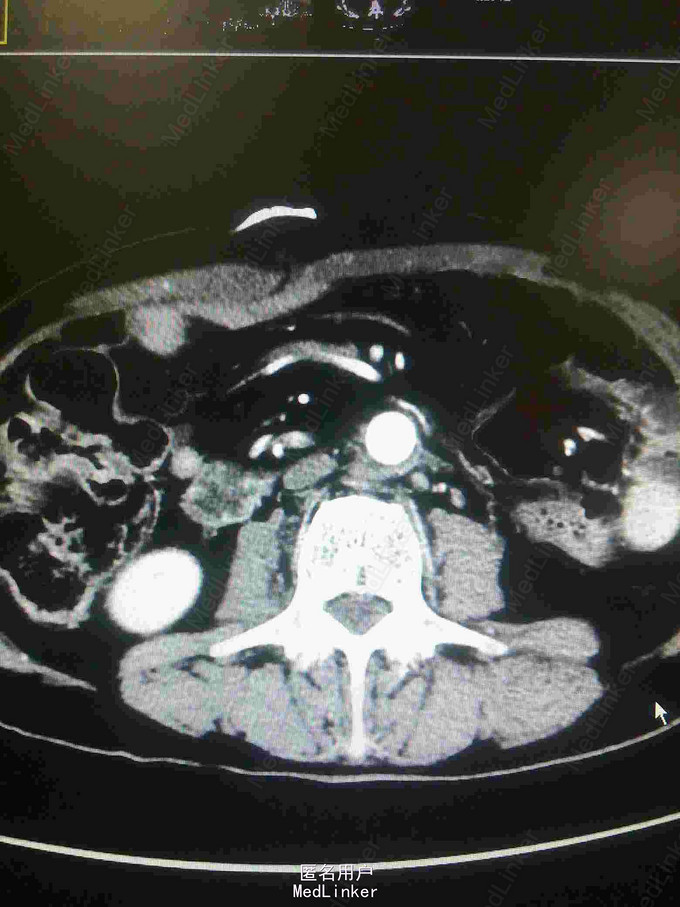

主诉:腰腹痛7月,加重一周。 病史:七月前发热后开始出现腰腹痛,呈持续性撕裂样痛,伴腹胀,症状反复。一周前腹痛症状加重。

体查:下腹部可触及搏动性包块。 辅助检查:腹部CT:腹主动脉假性动脉瘤并血栓形成,腰5椎体受侵蚀。血培养:沙门氏菌。

诊断:沙门氏菌感染性腹主动脉假性动脉瘤 处理:急诊行腹主动脉瘤切除人工血管置换术,术后予美罗培南抗感染8周,续以左氧氟沙星口服。